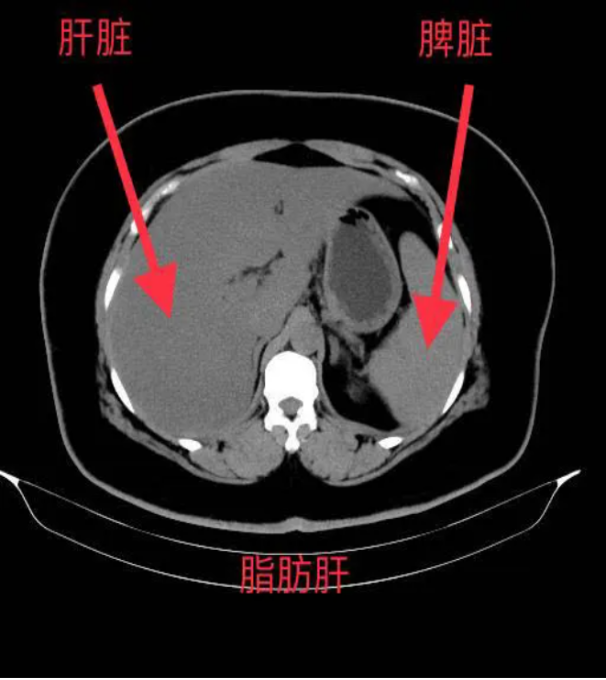

*肝脏密度降低:脂肪的CT值低于正常肝组织,因此脂肪肝在CT图像上表现为肝脏密度普遍降低,与脾脏密度相比更加明显。

*肝脾CT值比值:正常情况下,肝脏CT值高于脾脏,而脂肪肝患者的肝脾CT值比值会降低,甚至出现反转。